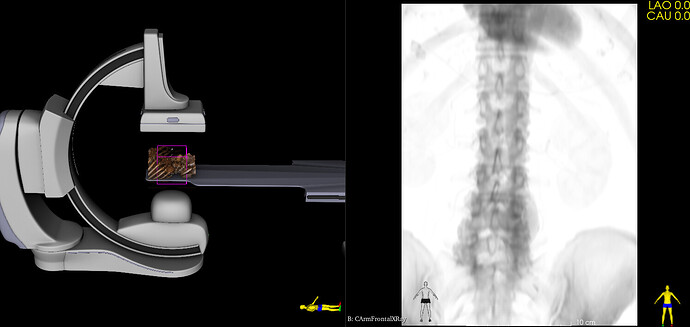

Virtual Cath Lab module has been recently added to SlicerHeart extension. This module simulates monoplane and biplane C-arm systems: provides 3D model of the C-arm, table, patient and generates simulated fluoroscopy images. Images can be either static (generated from 3D CT) or dynamic (generated from 4DCT). The module can also display cardiac devices (stents, occluders, clips, etc. provided by the Cardiac Device Simulator module) and virtual contrast filling (from image segmentation).

The module was developed for cardiac and vascular procedures, but it is well suited for simulation of any fluoroscopy guided procedures.

I’ve updated the module with the followings:

• Added detector rotation angle (no auto-rotation is available, but the rotation can be easily manually adjusted on the GUI)

• Default L arm angle is set the C-arm to be at the side of the table

• Projection beam is displayed (to make it easier to see the field of view in 3D)

• Detector size is configurable in the preset .csv files

Here is the procedural image with the C-arm oriented as simulated. I find it a faithful reproduction for a first try, and remain confident for subsequent ones.